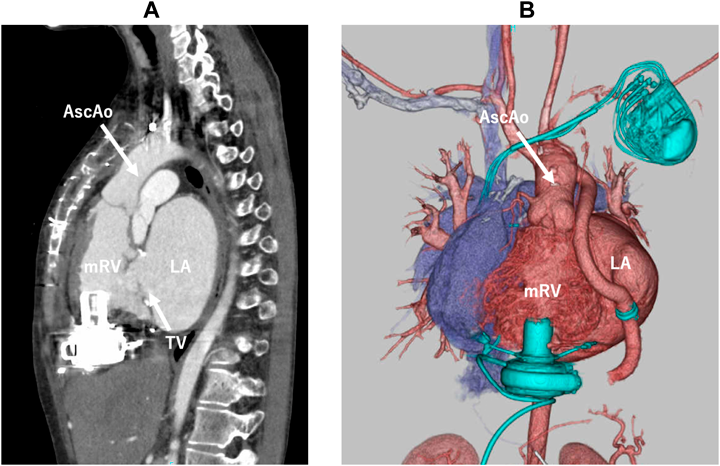

At the operation, a redo sternotomy was performed and a cardiopulmonary bypass was established through femoral cannulation. Under transesophageal echocardiogram guidance, the optimal inflow cannulation site was decided to avoid tricuspid tissue involvement. After aortic cross-clamping, trabeculation of the systemic RV was adequately resected and the HeartWare HVAD (Medtronic, Minneapolis, MN) was placed vertically from the RV diaphragmatic surface. The outflow graft was anastomosed to the left-lateral side of the ascending aorta. Postoperatively, the VAD flow had been stable with no evidence of tissue sucking or thrombus formation (Fig. 2). She was discharged home and waiting for heart transplantation as an outpatient.

Fig. 2 Postoperative images on contrast enhanced computed tomography (A) and 3D computed tomography (B) showing a vertically placed VAD through the diaphragmatic surface. No thrombus formation detected in the morphologically right ventricle.

AscAo, ascending aorta; LA, left atrium; mRV, morphologically right ventricle; TV, tricuspid valve.